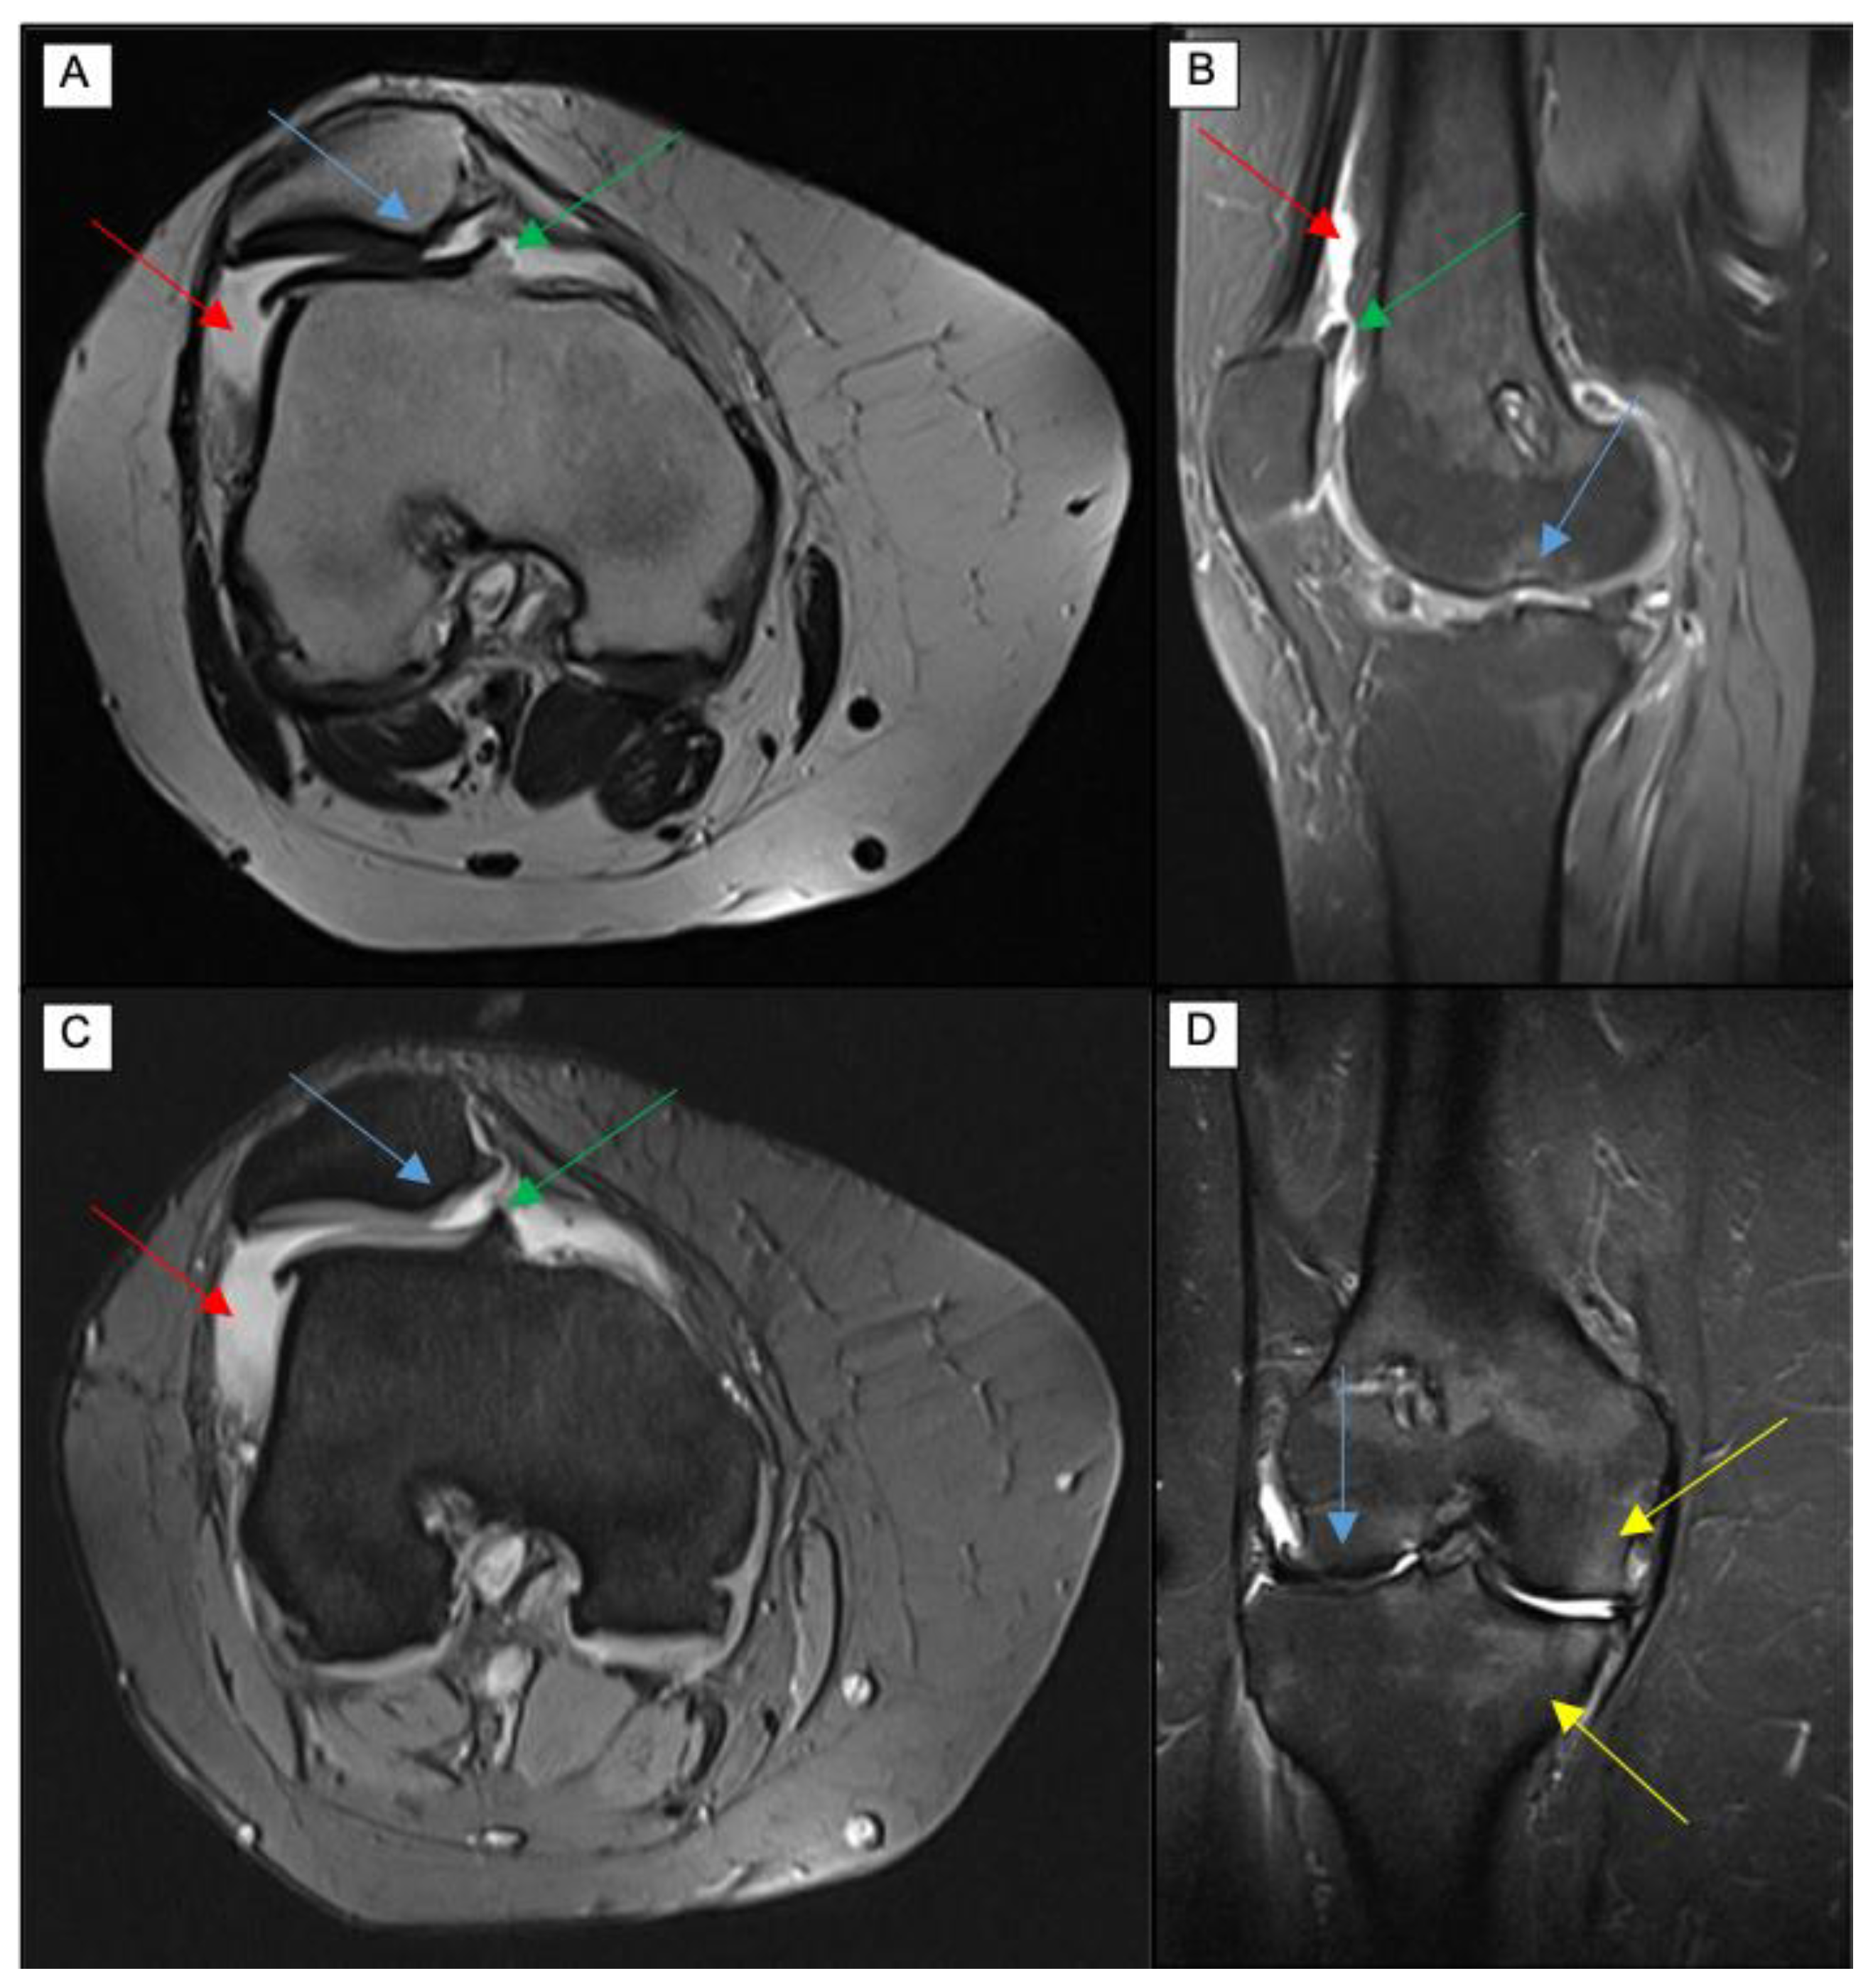

4.2. T2 Mapping